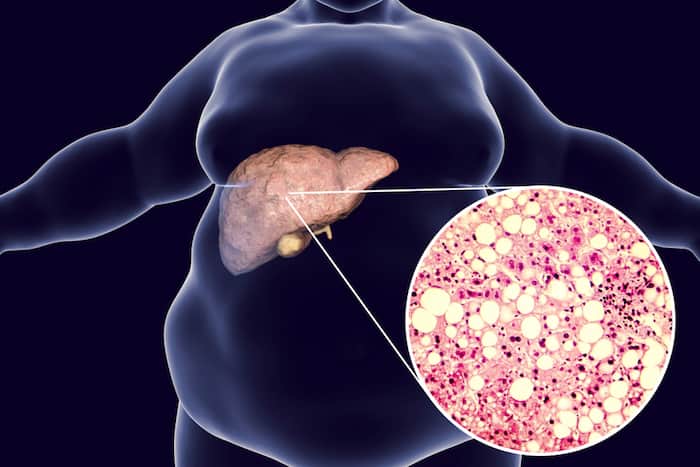

As its name implies, Nonalcoholic Fatty Liver Disease (NAFLD) is a medical condition wherein the liver accumulates excess fat that’s not from high and prolonged alcohol consumption.

Simple Fatty Liver or Steatosis

This liver condition is generally harmless. It involves fat buildup in the liver cells. Usually, this condition is accidentally diagnosed when tests are carried out for another medical condition.

Non-alcoholic steatohepatitis or NASH

As compared to simple fatty liver, this is a more serious type of NAFLD, wherein the liver becomes inflamed.

From the fatty liver, continuous fat accumulation may cause inflammation of the liver, causing nonalcoholic steatohepatitis or NASH.